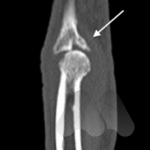

Cubital tunnel syndrome is a condition affecting the ulnar nerve as it travels behind the “funny bone” of the elbow. It is the second most common entrapment neuropathy in the upper limb behind carpal tunnel syndrome. It occurs due to the ulna nerve becoming compressed as it travels in a tunnel formed by bone, ligaments and muscle layers behind the inside of the elbow. The trapped ulnar nerve has difficulty carrying the electrical signals that supply sensation to the fingers and the power to the the muscles in the hand.